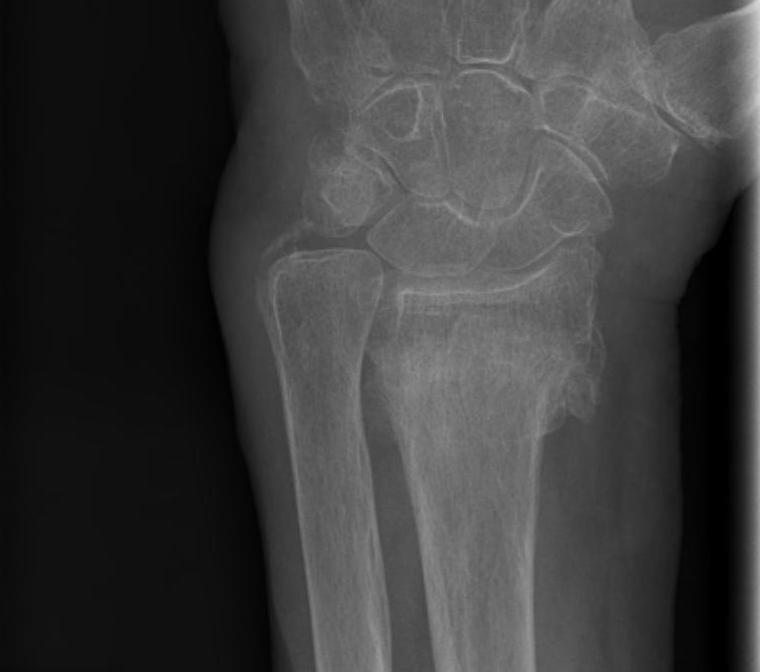

malunion

Dorsal tilt > 15 degrees Volar tilt > 10 degrees Articular step > 3 mm

malunion malunion

Xray

Bilateral xrays

PA film in neutral

- wrist neutral

- elbow & shoulder at 90°